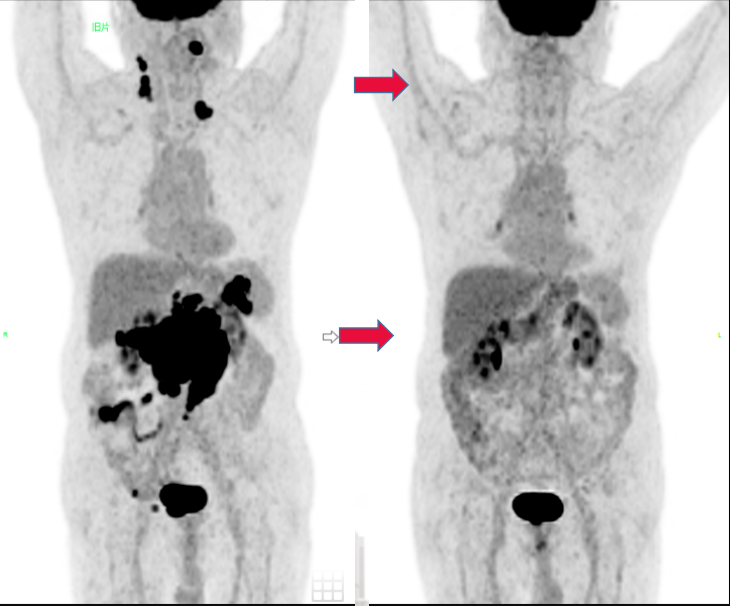

为进一步控制疾病进展,2025-03-13日起更换为匹妥布替尼 200mg qd+利妥昔单抗(600mg)、

匹妥布替尼联合治疗3周期,2025-05-20复查PET-CT结果示颈腹盆处多发淋巴结较前明显减少,代谢明显减低,疗效评估为完全代谢缓解(CMR)。

图2 匹妥布替尼联合治疗前后PET-CT结果